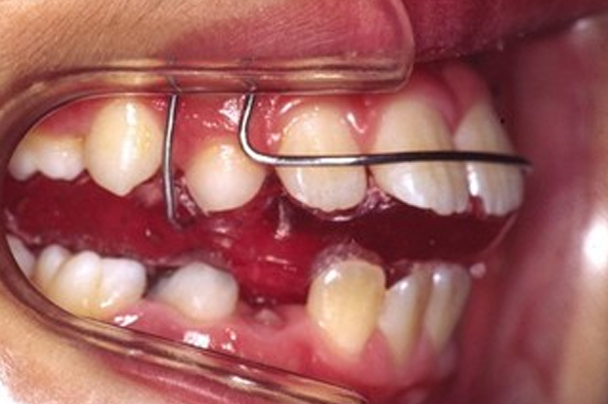

| 治療に用いた装置 | アクチバトール |

上の前歯と下の前歯の間に1センチくらいの距離があり、口が閉じにくく見た目が気になるとのこと。また、前歯のかみ合わせがとても深いため、下の前歯と上あごの粘膜が接触しており、上あごの粘膜が炎症を起こして痛みのある状態でした。この患者さんは「出っ歯」と「過蓋咬合」の複合タイプのかみ合わせでした。出っ歯というと上の前歯が前方に出ている様子を想像しますが、この患者さんを検査したところ下あごが平均よりもかなり後ろに位置していることがわかりました。下あごの成長が弱い「骨格性上顎前突」という診断名でした。「アクチバトール」という取り外し可能な装置を使用することになりました。この装置を口の中に入れて口を閉じると、下あごを「前咬み」した状態になります。下あごを前咬みした状態を維持することで、成長期の患者さんであれば下あごの前方成長が促されます。また、この装置は前歯の深いかみ合わせ(過蓋咬合)を改善する働きもあります。この装置は睡眠時を中心に一日12時間使用するものですが、長時間使用した方が効果的であるため、毎日学校から帰宅したらすぐに装置を装着するようにお願いしました。